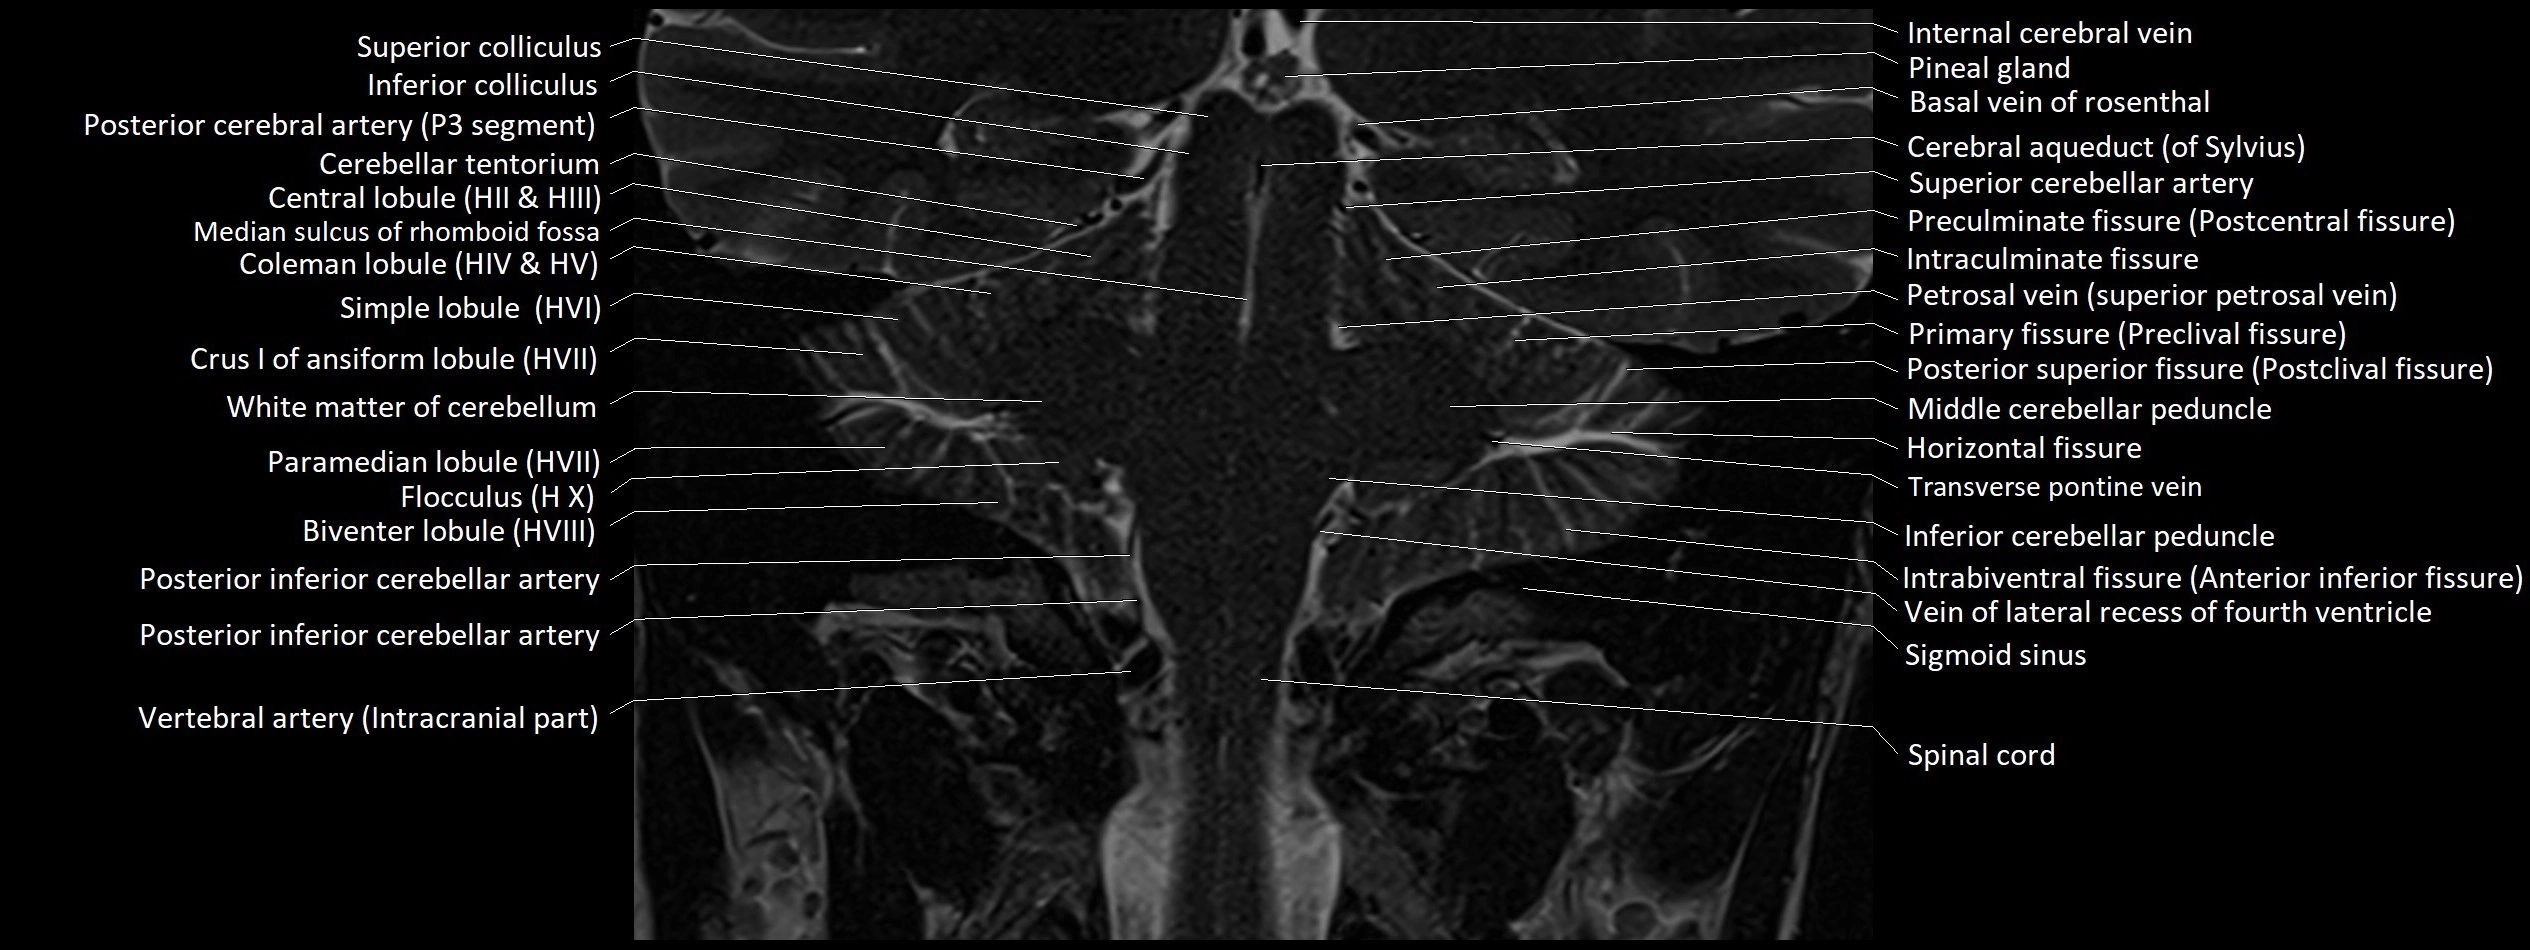

MRI images